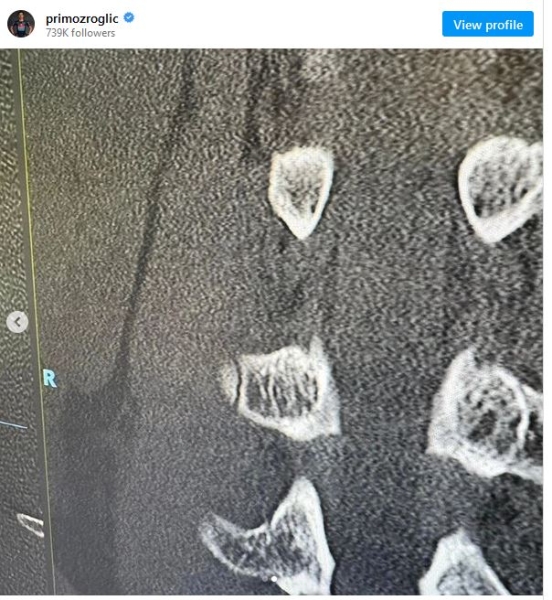

Примож Роглич: «Жизнь иногда становится не такой простой, правда? Дальнейшие обследования после падения на Тур де Франс показали, что у меня перелом lwk3 поперечного отростка позвоночника в пояснице, поэтому на прошлой неделе я восстанавливался в Red Bull Athlete Performance Center, где обо мне позаботились наилучшим образом.